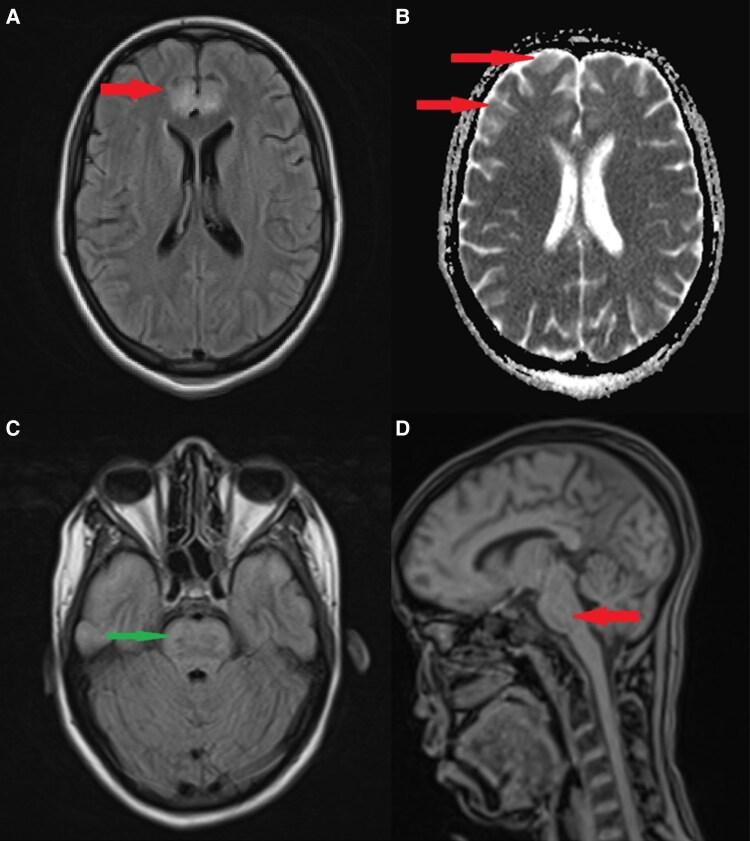

Diabetic ketoacidosis (DKA)-associated brain injury is a rare but serious complication, typically occurring early during metabolic correction and associated with a poor prognosis. We report the case of an 18-year-old college student admitted to the intensive care unit with severe DKA, characterized by profound metabolic acidosis and marked electrolyte imbalances, including hypokalemia, hypernatremia, and hyperchloremia. Within hours, she developed altered mental status and generalized seizures. Brain magnetic resonance imaging (MRI) revealed diffuse cortical and brainstem abnormalities, suggestive of cytotoxic cerebral edema. She was managed with continuous sedation, mechanical ventilation, intravenous insulin, potassium supplementation, enteral nutrition, and gradual metabolic correction. Her neurologic status improved within a few days, and follow-up MRI showed partial regression of the lesions. She was subsequently transferred to the endocrinology department and ultimately regained full cognitive and physical function. This case underscores the importance of early recognition, close neurologic monitoring, timely neuroimaging, and tight metabolic and osmotic control to optimize outcomes in patients with DKA-associated brain injury.

糖尿病酮症酸中毒(DKA)相关的脑损伤是一种罕见但严重的并发症,通常发生在代谢纠正的早期,且预后不良。我们报告一例18岁大学生因严重DKA入住重症监护病房的病例,其特征为严重代谢性酸中毒和明显的电解质失衡,包括低钾血症、高钠血症和高氯血症。数小时内,她出现了精神状态改变和全身性癫痫发作。脑磁共振成像(MRI)显示弥漫性皮质和脑干异常,提示细胞毒性脑水肿。她接受了持续镇静、机械通气、静脉注射胰岛素、补钾、肠内营养和逐步的代谢纠正治疗。几天后她的神经状态有所改善,随访MRI显示病变部分消退。她随后被转至内分泌科,最终恢复了完全的认知和身体功能。该病例强调了早期识别、密切的神经监测、及时的神经影像学检查以及严格的代谢和渗透压控制对于优化DKA相关脑损伤患者预后的重要性。